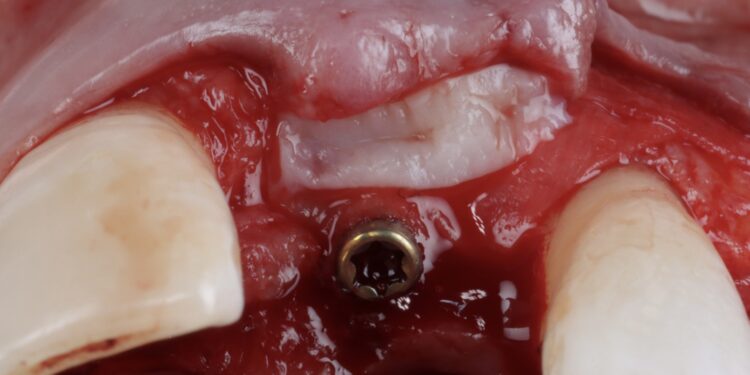

Once the orthodontic treatment was completed, the site was re-evaluated, and it was clear to see that the gingival zenith had significantly improved. The patient was advised that without re-contouring the mesial aspect of the contralateral central incisor there would be a midline black triangle. She rejected the option of composite addition to alter the triangular shape of the UR1 and thus we proceeded to complete the treatment without this. The implant was placed with simultaneous buccal GBR & connective tissue graft following a transmucosal approach. Following a healing period of 4 months, the restorative treatment was initiated with a temporary crown to develop the emergence profile. Once the gingival zeniths had been matched, the patient was delivered a permanent screw retained crown.